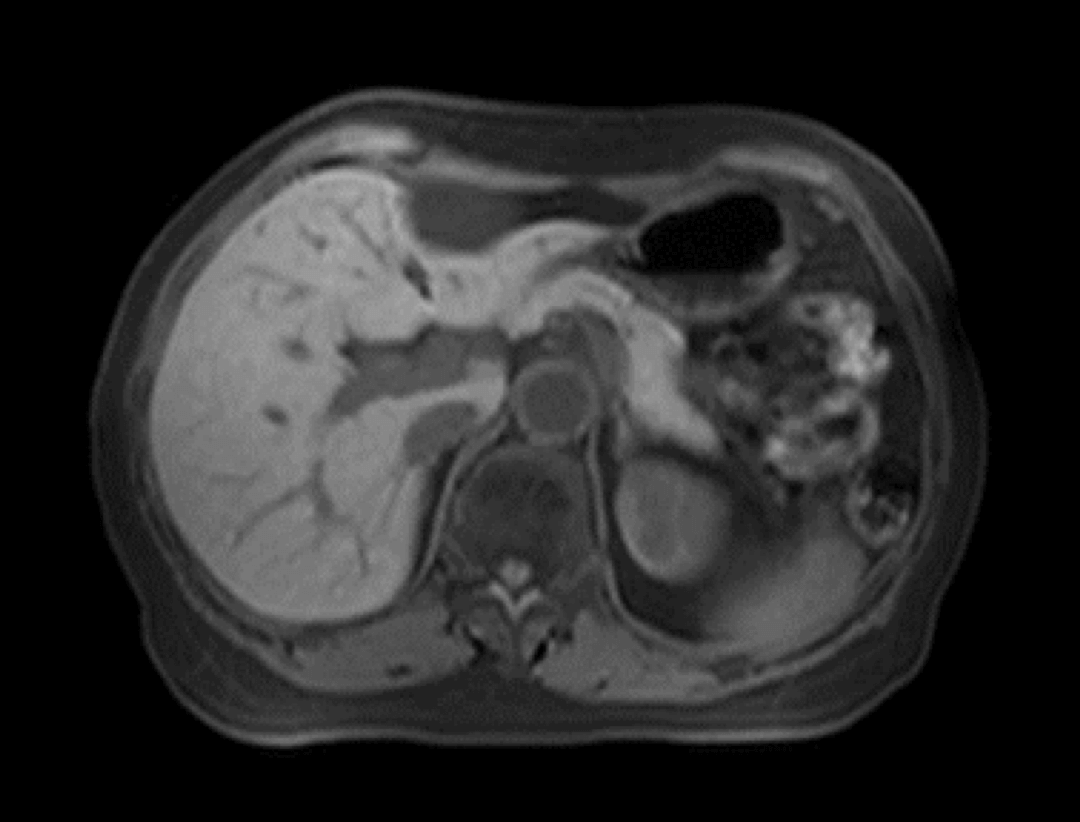

W przypadku wzmocnienia dynamicznego skanowania jamy brzusznej platforma uCS®2.0 może przyspieszyć akwizycję 16-krotnie, pozwalając wyraźnie uchwycić ciągłe dynamiczne zmiany sygnałów tkankowych.

Jama brzuszna